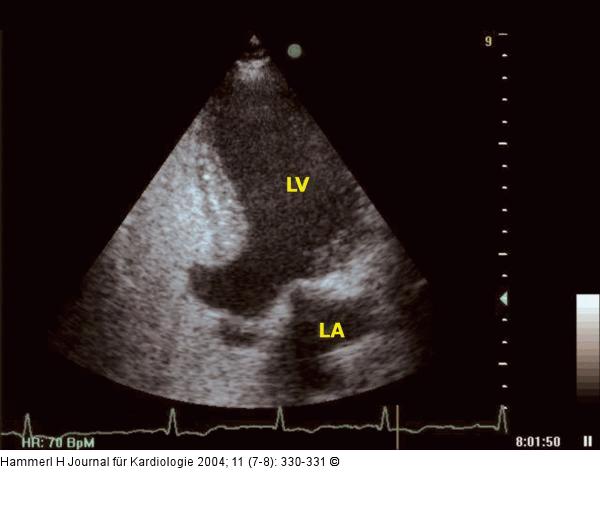

Abbildung 4: Interventrikuläres Septum - Aneurysma Apikaler Vierkammerblick - Echokontraststudie: Kontrastierung des rechten Vorhodes/rechten Ventrikels ohne AUftreten eine Wash-out-Phänomens im Bereich des Aneurysmas; LA = linker Vorhof; LV =linker Ventrikel |

Abbildung 4: Interventrikuläres Septum - Aneurysma

Apikaler Vierkammerblick - Echokontraststudie: Kontrastierung des rechten Vorhodes/rechten Ventrikels ohne AUftreten eine Wash-out-Phänomens im Bereich des Aneurysmas; LA = linker Vorhof; LV =linker Ventrikel |